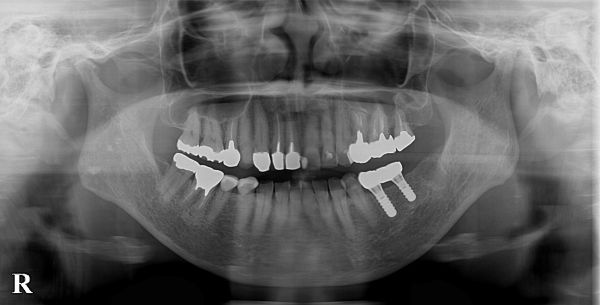

また、こちらが初診時のレントゲン写真になります。

左下5番目の歯も同様で、大きな金属の土台を外して虫歯を取ると、ほとんど歯茎の外側には健康な歯が残らない状態となります。また、レントゲン写真を見ると、とても太い金属の土台が入っているため、残っている歯がとても薄くなってしまっており、ブリッジで大きな力をかけた際に歯根破折(歯の根のヒビ)が起こる可能性が非常に高いことが予想されます。

また、下顎のインプラント治療を行う際は、下顎管という感覚神経(下歯槽神経)が入った管に注意をしなければなりませんが、今回は神経との距離も十分にあり、極めて安全にインプラント治療が行えるケースでありました。今回は、予算の都合上、2本のインプラントで2本の歯を作ることとしました。

ジルコニアクラウンが完成しましたので、微調整を行い、セットしました。こちらがセット後の写真とレントゲン写真になります。